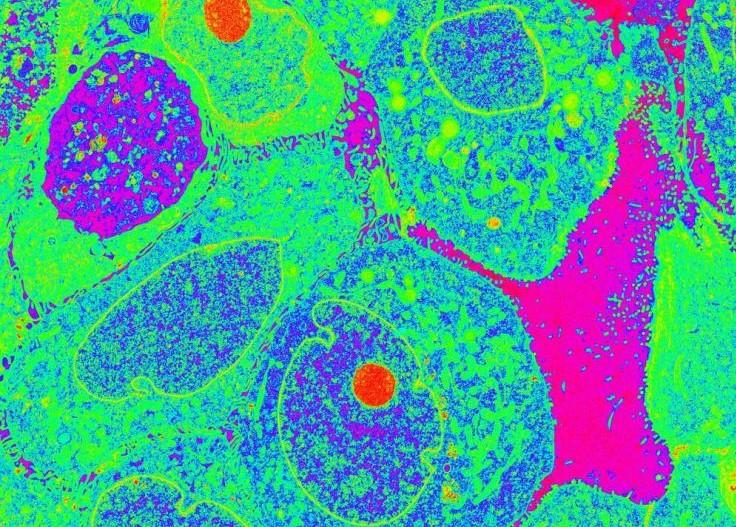

We investigate the evolution and adaptations of triple negative breast cancers (TNBCs) as they resist therapies and metastasize to secondary organs with a focus on mitochondria, metabolism, and intra-organellar communication. We leverage state-of-the-art technologies in clinically relevant experimental models of TNBC (namely human patient-derived xenograft, PDX, mouse models, and human tumor cell lines) to discover important mechanisms underpinning resistance. We translate those insights into preclinical testing of mitochondria-targeting therapies. Our ultimate goal is to translate our laboratory findings into clinical trials to benefit TNBC patients.